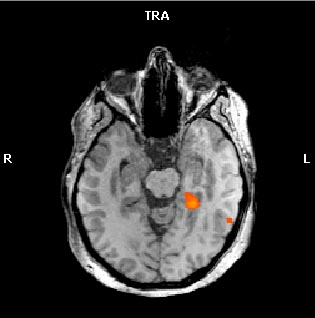

Lo resultados que hemos obtenido en pacientes con ELT concuerdan con la literatura previa, ya que existe una organización atípica de la memoria en este tipo de pacientes donde se obtienen activaciones con una distribución preferentemente contralesional (ver Figuras 2A y 2B).

Activación cerebral de predominio izquierdo durante la tarea de codificación de imágenes (2A) y “paseo por tu ciudad” (2B) en un paciente con ELT derecho.

| 2A.- Codificación de imágenes |

2B.- “Paseo por tu ciudad” |